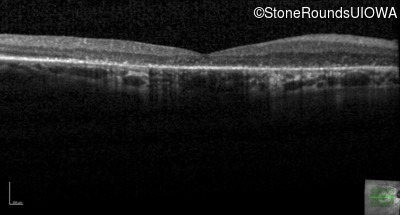

Cone-Rod Dystrophy (IA1b)

Age at visit: 58 years

This 58 year old woman first noticed a gap in the vision of her left eye at age 46.

Diagnosis & molecular findings

Disease Gene Allele 1 variant(s) Allele 2 variant(s) Inheritance mode

Cone-Rod Dystrophy CRB1 Cys948Tyr (T)GT>(T)AT Asp165 del9cagGATGGAATT AR